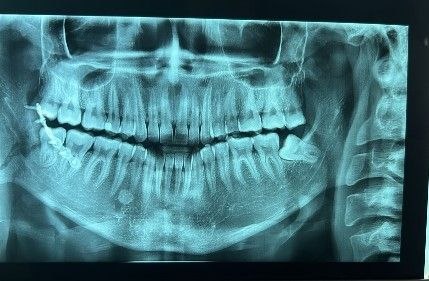

En el Centro Maxilofacial, brindamos atención de emergencia las 24 horas, los 7 días de la semana para el manejo de fracturas de mandíbula, utilizando tratamientos de vanguardia que permiten una rápida recuperación.

Aplicamos la técnica intrabucal de reducción de fractura sin cicatrices, logrando resultados funcionales y estéticos óptimos para nuestros pacientes.